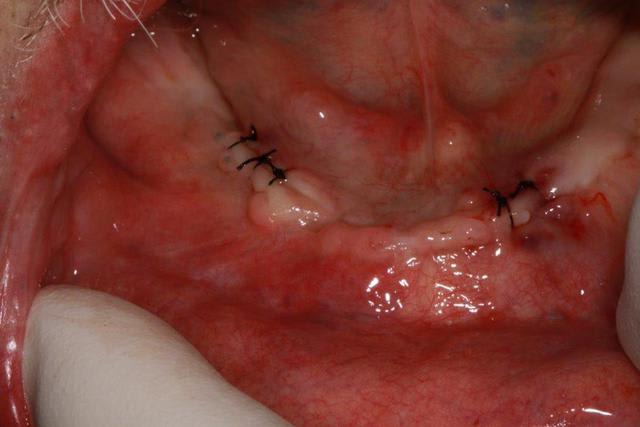

Or il fallait enlever 34/35 et 44/45...ce que j'ai fait avec précaution, nettoyage soigneux éponges de gelatemp et sutures.

8 jours après, cicatrisation nickel, donc je n'hésite pas pour les implants à la mandibule, et je propose un partiel maxillaire avec conservation des incisives....

cicatrisation à 8 jours...ras donc ce sera implants pour le bas.

En flapless